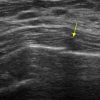

Gãy xương sườn

» Thông tin: Nữ giới – 52 tuổi.

» Lâm sàng: Chấn thương ngực.